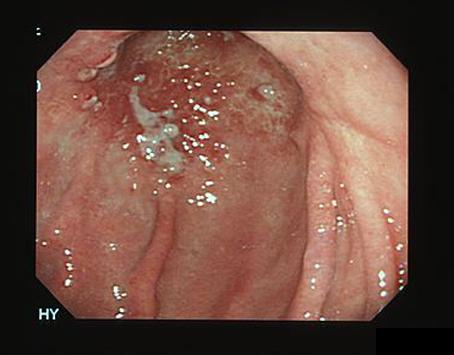

症例提示(所在地,施設名等): 東京都・ 国立がんセンター中央病院

疾患(病理主体)の分類悪性リンパ系腫瘍/悪性リンパ腫

部位(臓器別)胃(部位)/前庭

検査方法内視鏡

腫瘍の肉眼分類0型(表在型)/IIc型(IIc)

病変の最大径(ミリ)40以上

腫瘍の深達度sm